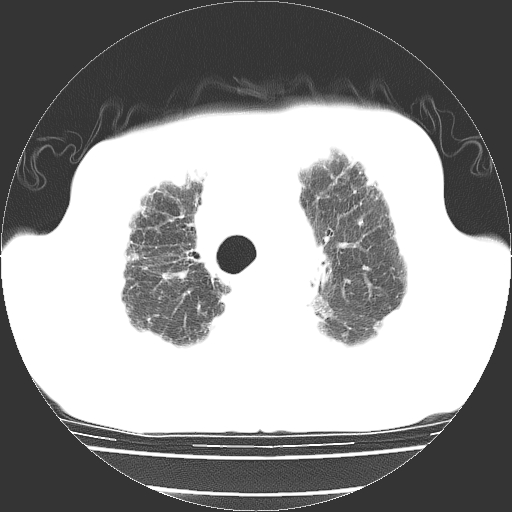

标题: CT25149:男,69岁,反复咳嗽、咳痰五年余,呼吸困难三天。 [打印本页]

男,69岁,反复咳嗽、咳痰五年余,呼吸困难三天。

慢支伴感染、肺气肿、肺心病

慢支伴感染、肺气肿、肺心病!支持!另:间质纤维化!

两肺间质性炎症并感染,左上叶肉芽肿

考虑慢性间质性肺炎并肺间质纤维化。

慢支伴感染、肺气肿、肺心病。双肺间质性改变(间质纤维化)。